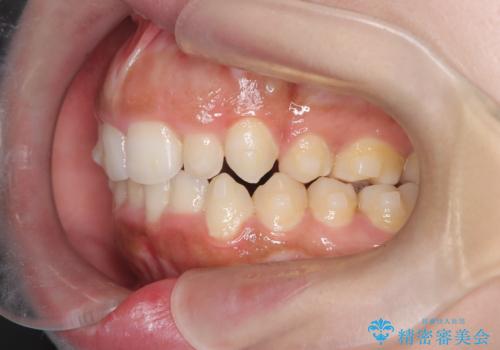

- 「前歯が出ていて並びも悪いのが気になる」との主訴で来院されました。診察の結果、上顎前歯の前突と中等度の叢生(ガタつき)が認められ、歯がきれいに並ぶスペースが不足していました。横顔のバランスと歯並びの両方を整えるため、上顎の左右の第一小臼歯2本を抜歯し、前歯を内側に下げながら歯列全体を整える治療計画を立てました。

患者さんのご希望もあり、取り外しが可能で目立ちにくいインビザライン(マウスピース矯正)を選択。抜歯スペースを活用しながら、叢生と前突感の改善を同時に目指しました。

治療はインビザラインによって進め、抜歯スペースを使って前歯を内側に引き込みながら、歯のガタつきも順に整えていきました。初期の段階で前歯の見た目が大きく変わり、患者さんにも「印象が柔らかくなった」と非常に喜んでいただけました。